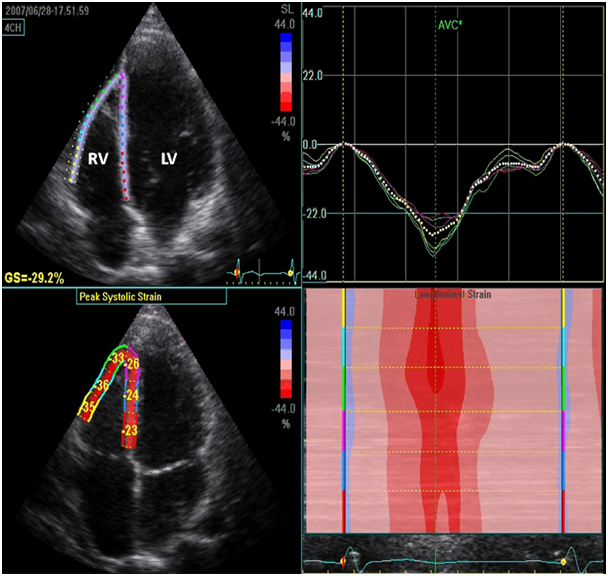

льный стрейн

Продольный стрейн 105 фото